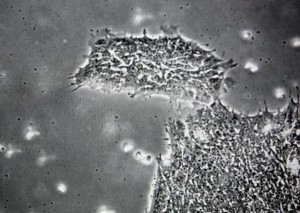

約翰-霍普金斯醫(yī)學院和內布拉斯加大學的科學家們在進行一項咽喉微生物研究時偶然發(fā)現(xiàn)了這種病毒。令人驚奇的是,研究人員發(fā)現(xiàn)健康人群咽喉中的DNA與一種已知的綠藻類病毒DNA相匹配。

參與研究的90名志愿者當中,40名的藻類病毒監(jiān)測呈陽性。而這些人在視覺處理的速度和準確度的測定中表現(xiàn)的更加糟糕。而在注意力測試中他們的得分也比其他人低。人體攜帶者萬億細菌、病毒和菌類,大多數(shù)都是無害的。但是這項研究的發(fā)現(xiàn)表明,有一些微生物雖然不會危害個人健康,但卻會對人的認知功能產生不利的影響。(過客/編譯)